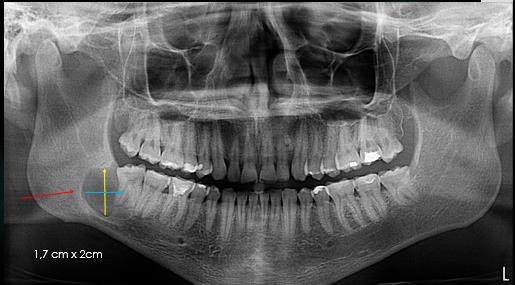

Sse procede a evaluar y analizar ortopantomografia inicial, lo cual hace referencia a una lesion de 1,7 cm x 2cm aproximadamente ya que esto es referencial, evaluación de imágenes de TAC,  analisis de informe imagienológico,       exámenes     de laboratorio que arrojan leve aumento de la serie blanca asociada a infección, ya con todos estos datos clinicos e imagienológicos, se  procede a la discusión y planificacion quirúrgica en la que se decide su remocion  completa y no parcial, realizar estudio histopatológico esperando los resultados bajo conducta espectante si amerita un segundo tiempo quirúrgico.

Figura 4.  Ortopantomografia con medidas estimadas del tamaño de la lesión. Fuente Palima (2016).

Figura 8. Ortopantomografía control, se puede observar la formación ósea y recuperación del techo del canal man dibular

Fuente Palima (2018).